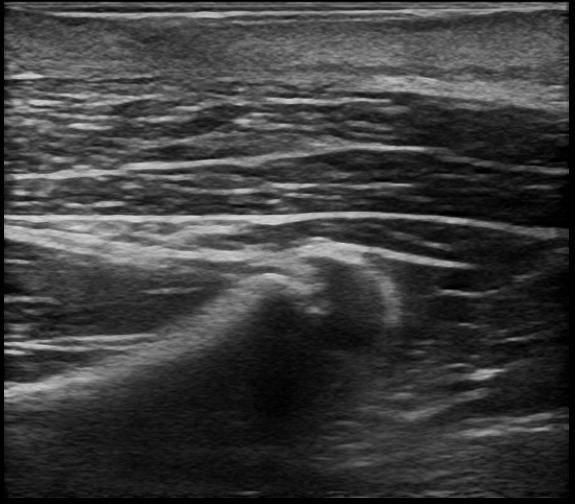

術後半年後には、わずかな変形は認められるものの、傷跡は目立たず、超音波検査で再発がないことを確認し、治療を終了しました。

術後半年後 ①

術後半年後 ②